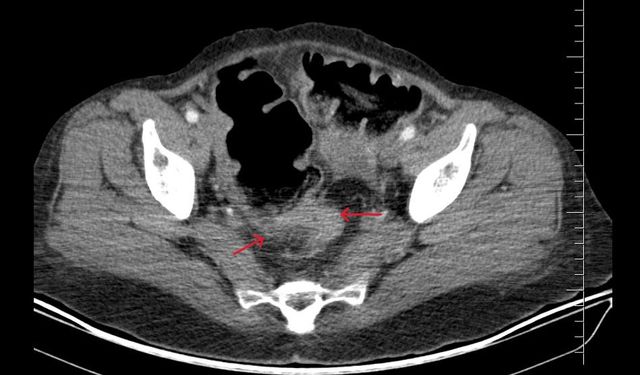

Viranşehir Devlet Hastanesi’nde Büyük Böbrek Kisti Kapalı Yöntemle Başarıyla Alındı.

Balıklıgöl Devlet Hastanesi’nde 25 Santimetrelik Dev Kist Başarıyla Alındı